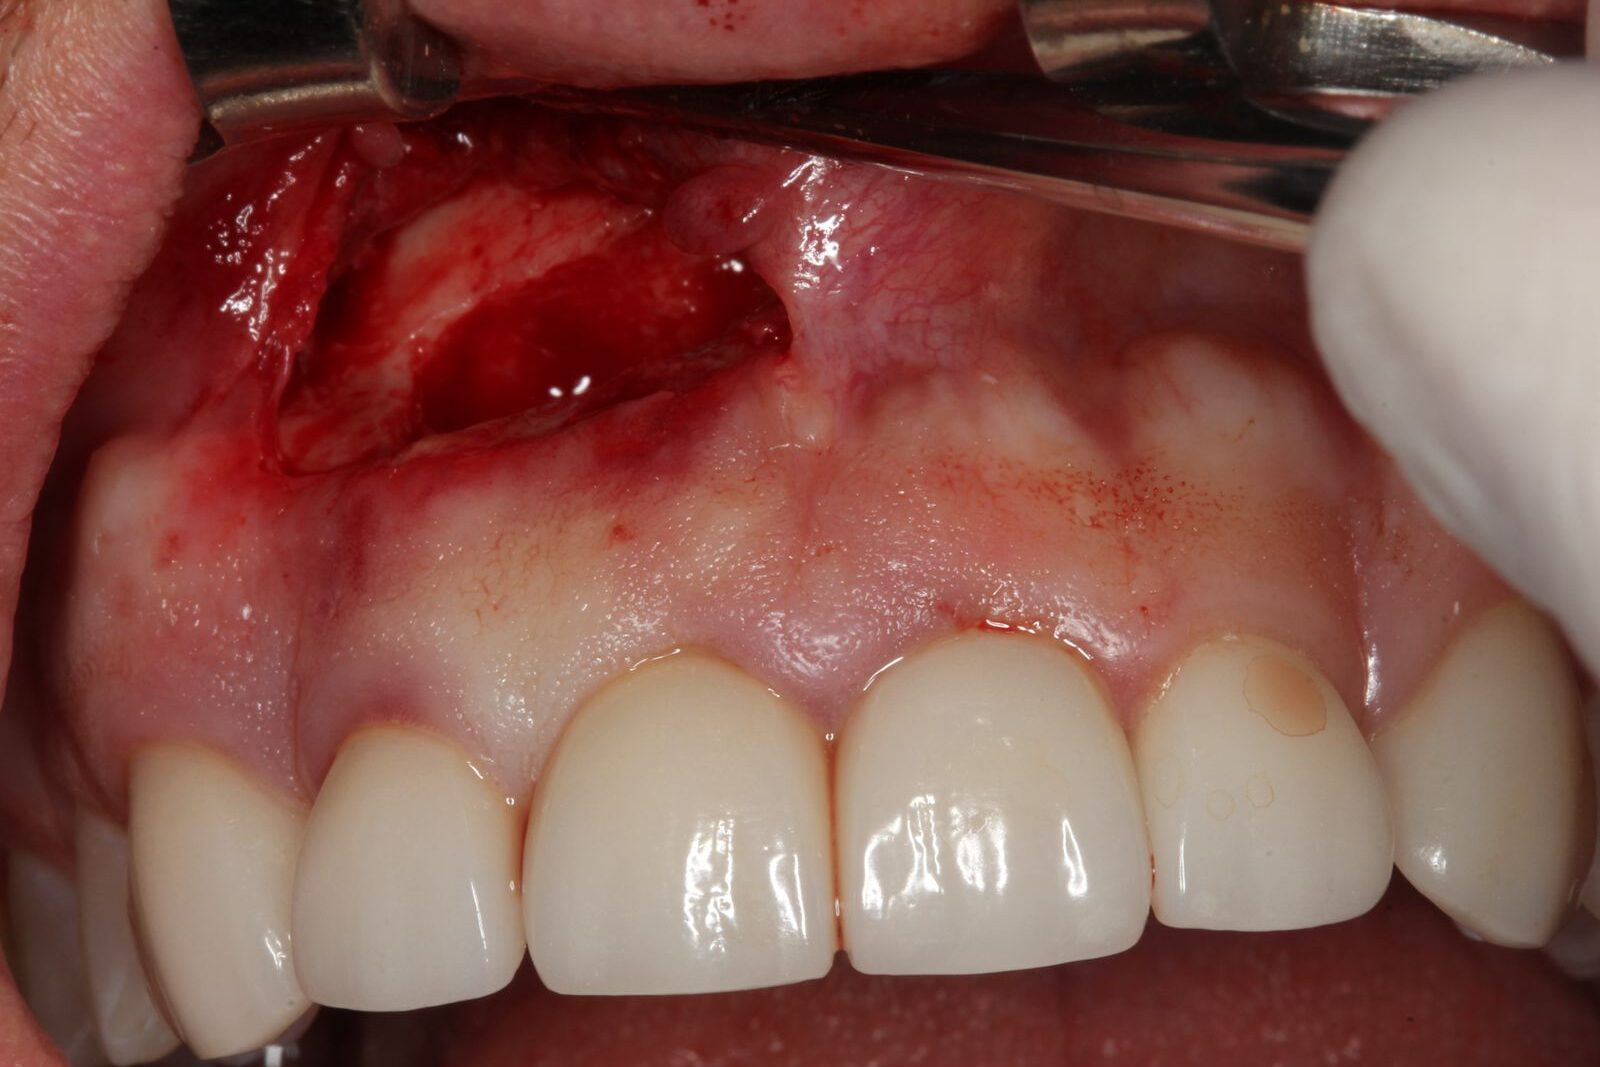

Uma incisão na gengiva com bisturi, permitindo acesso à região óssea. A exposição da área infectada muitas vezes já revela a gravidade da lesão, seguida da drenagem do conteúdo infeccioso, quando presente.